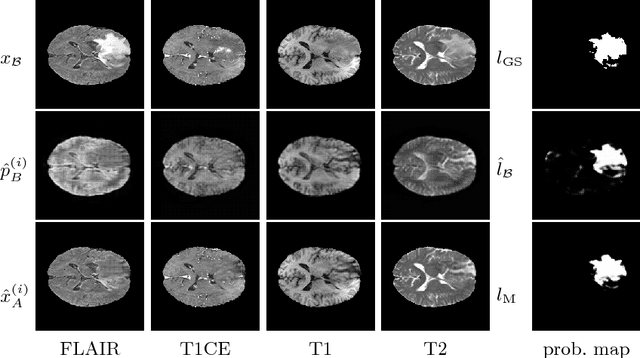

Abstract:Quantification of cerebral white matter hyperintensities (WMH) of presumed vascular origin is of key importance in many neurological research studies. Currently, measurements are often still obtained from manual segmentations on brain MR images, which is a laborious procedure. Automatic WMH segmentation methods exist, but a standardized comparison of the performance of such methods is lacking. We organized a scientific challenge, in which developers could evaluate their method on a standardized multi-center/-scanner image dataset, giving an objective comparison: the WMH Segmentation Challenge (https://wmh.isi.uu.nl/). Sixty T1+FLAIR images from three MR scanners were released with manual WMH segmentations for training. A test set of 110 images from five MR scanners was used for evaluation. Segmentation methods had to be containerized and submitted to the challenge organizers. Five evaluation metrics were used to rank the methods: (1) Dice similarity coefficient, (2) modified Hausdorff distance (95th percentile), (3) absolute log-transformed volume difference, (4) sensitivity for detecting individual lesions, and (5) F1-score for individual lesions. Additionally, methods were ranked on their inter-scanner robustness. Twenty participants submitted their method for evaluation. This paper provides a detailed analysis of the results. In brief, there is a cluster of four methods that rank significantly better than the other methods, with one clear winner. The inter-scanner robustness ranking shows that not all methods generalize to unseen scanners. The challenge remains open for future submissions and provides a public platform for method evaluation.